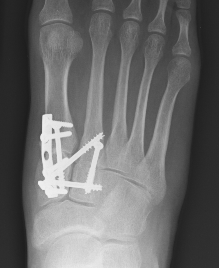

AP view

- 1st metatarsal to medial cuneiform - screw

- 2nd metatarsal to intermediate cuneiform - screw

- medial cuneiform to base of second metatarsal - screw

+/- medial cuneiform to intermediate cuneiform - screw